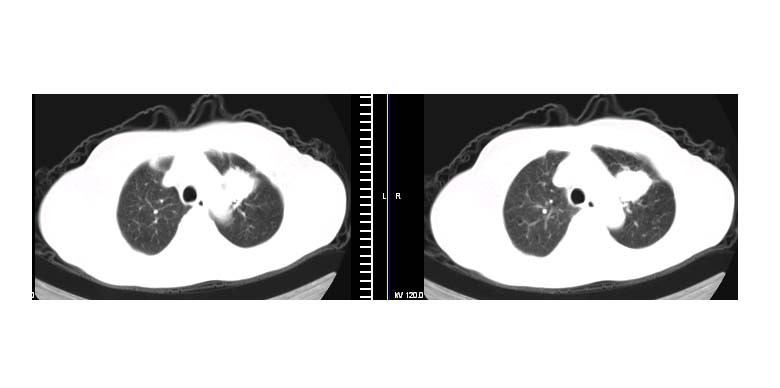

标题: CT11087:男性,82.咳嗽一周.抗炎治疗4-5天效果不明 [打印本页]

标题: CT11087:男性,82.咳嗽一周.抗炎治疗4-5天效果不明

左上肺实质性肿块,浅分叶 毛糙 胸膜凹陷征 纵隔淋巴结肿大——支持:左肺上叶周围型肺癌!

左上肺软组织肿块,有分叶,短毛刺,气管旁间隙见有肿大淋巴结,考虑左上周围型肺癌伴纵隔淋巴结转移。

考虑左上肺周围性肺癌(实性病灶有分叶,毛刺)可能性大。

左肺上叶尖段周围型肺癌伴左肺门淋巴结转移。